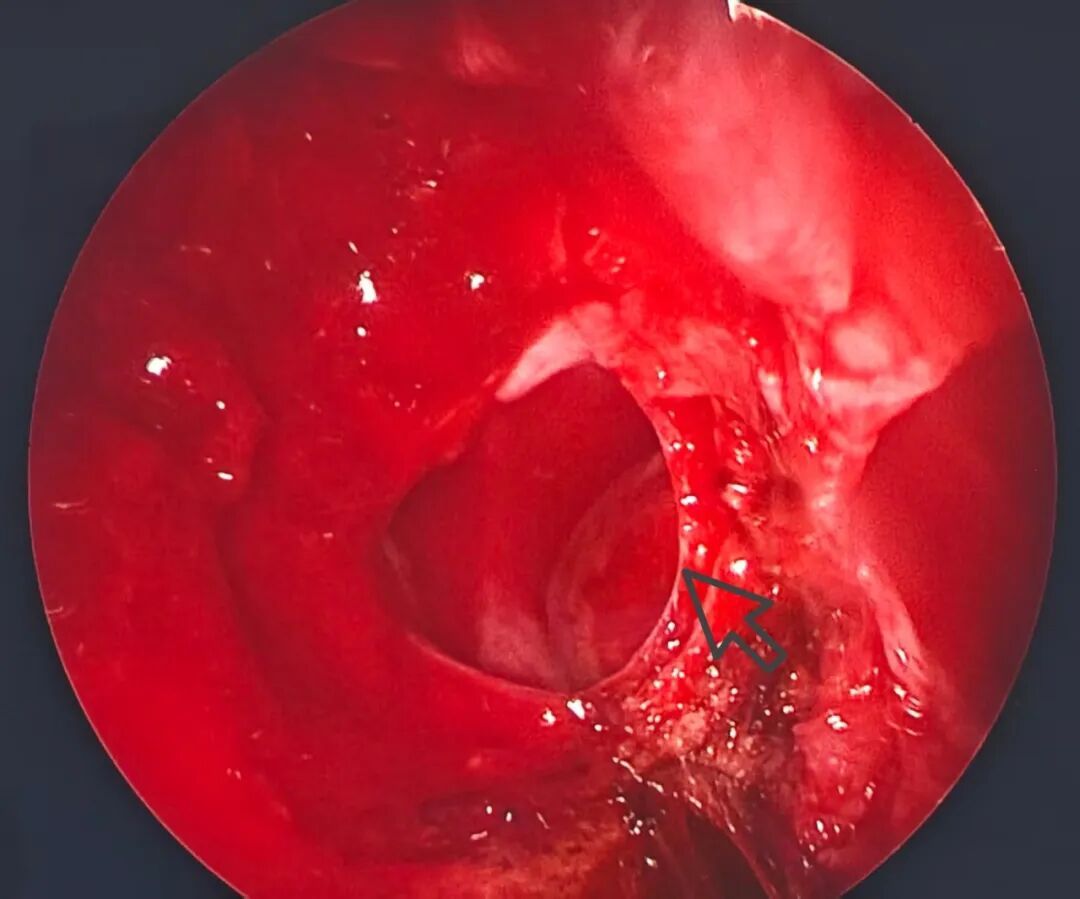

什么是脑脊液鼻漏? 想象颅脑好比一个浴缸,里面装满了水和脑组织,水代表脑脊液。通常情况下,水会安全地待在浴缸内,不会溢出。如果各种原因导致浴缸底部或侧面出现了一个小裂缝,水就会开始从这个裂缝渗漏出来,进而通过鼻道这个下水道流出来了。 非外伤和手术,自发性是何缘由? 脑脊液鼻漏分为创伤性和非创伤性。其中创伤多为外伤造成,其次为医源性手术所致。非创伤性原因多为颅内肿瘤或脑水肿所致的颅内高压;少数为先天缺损、颅底骨质薄弱导致的自发性脑脊液鼻漏,或称为“原发性脑脊液鼻漏”。因其起病隐匿,临床症状多表现为单侧清水样鼻漏,并常因特定的头位加重脑脊液的流出,可无其他合并症状,因此易误诊漏诊。 该疾病是不是很严重? 持续的脑脊液流失可能导致慢性颅内低压,患者可能会经历顽固性头痛,尤其是在站立或坐起时,因为这种姿势会加剧脑脊液的进一步流失。还有患者会出现嗅觉减退甚至失嗅。 脑脊液漏出打破了脑和外界的天然屏障,这大大增加了细菌和其他病原体侵入的机会,可能导致脑膜炎等严重感染。因此,一旦确诊建议积极治疗。 治疗方法有哪些? 对于首次发生、病程短的自发性脑脊液鼻漏病例,可尝试保守治疗。包括保持30°斜坡卧位,避免咳嗽、喷嚏及擤鼻涕等可能增加颅内压的动作。酌情使用抗菌药物及甘露醇脱水。如患者鼻漏量较小,无其他并发症状,可观察2周~1月。如患者鼻漏量较快及较大、短期内无好转迹象,说明漏口较大,自愈可能性小,应尽快行手术治疗。 目前鼻内镜下修复脑脊液鼻漏是该疾病外科治疗的首选手段。其优点在于: 1.创伤小,患者术后恢复快,住院时间短。 2.术野暴露满意、清晰,可利用多角度鼻内镜观察筛顶、筛板及蝶窦。 3.术中可直视到脑脊液漏出,判断漏口位置较准确。 4.大部分病例可保留中鼻甲,对鼻功能影响小。 图:箭头指示左鼻腔脑脊液鼻漏处及脑膜脑膨出 目前周先生术后两个月复查,患者主诉一切正常,鼻内镜下检查显示愈合良好。非常感恩医护人员,开心地回家了。 供稿:苏甜甜 审核:邓 月、石 崧 校审:戴 云 预约就诊请关注公众号: (配图源自网络,如有侵权请通知删除) 欢迎关注同仁医院官方微信服务